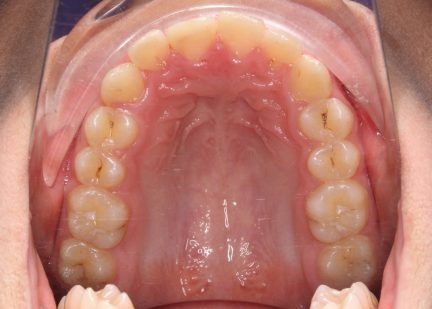

Classe II div 1, surplomb accru, rétrognathie mandibulaire, articulation profonde, arcades étroites, arcades asymétriques, déviation de la ligne médiane mandibulaire, décalage de la ligne médiane, chevauchement

État initial